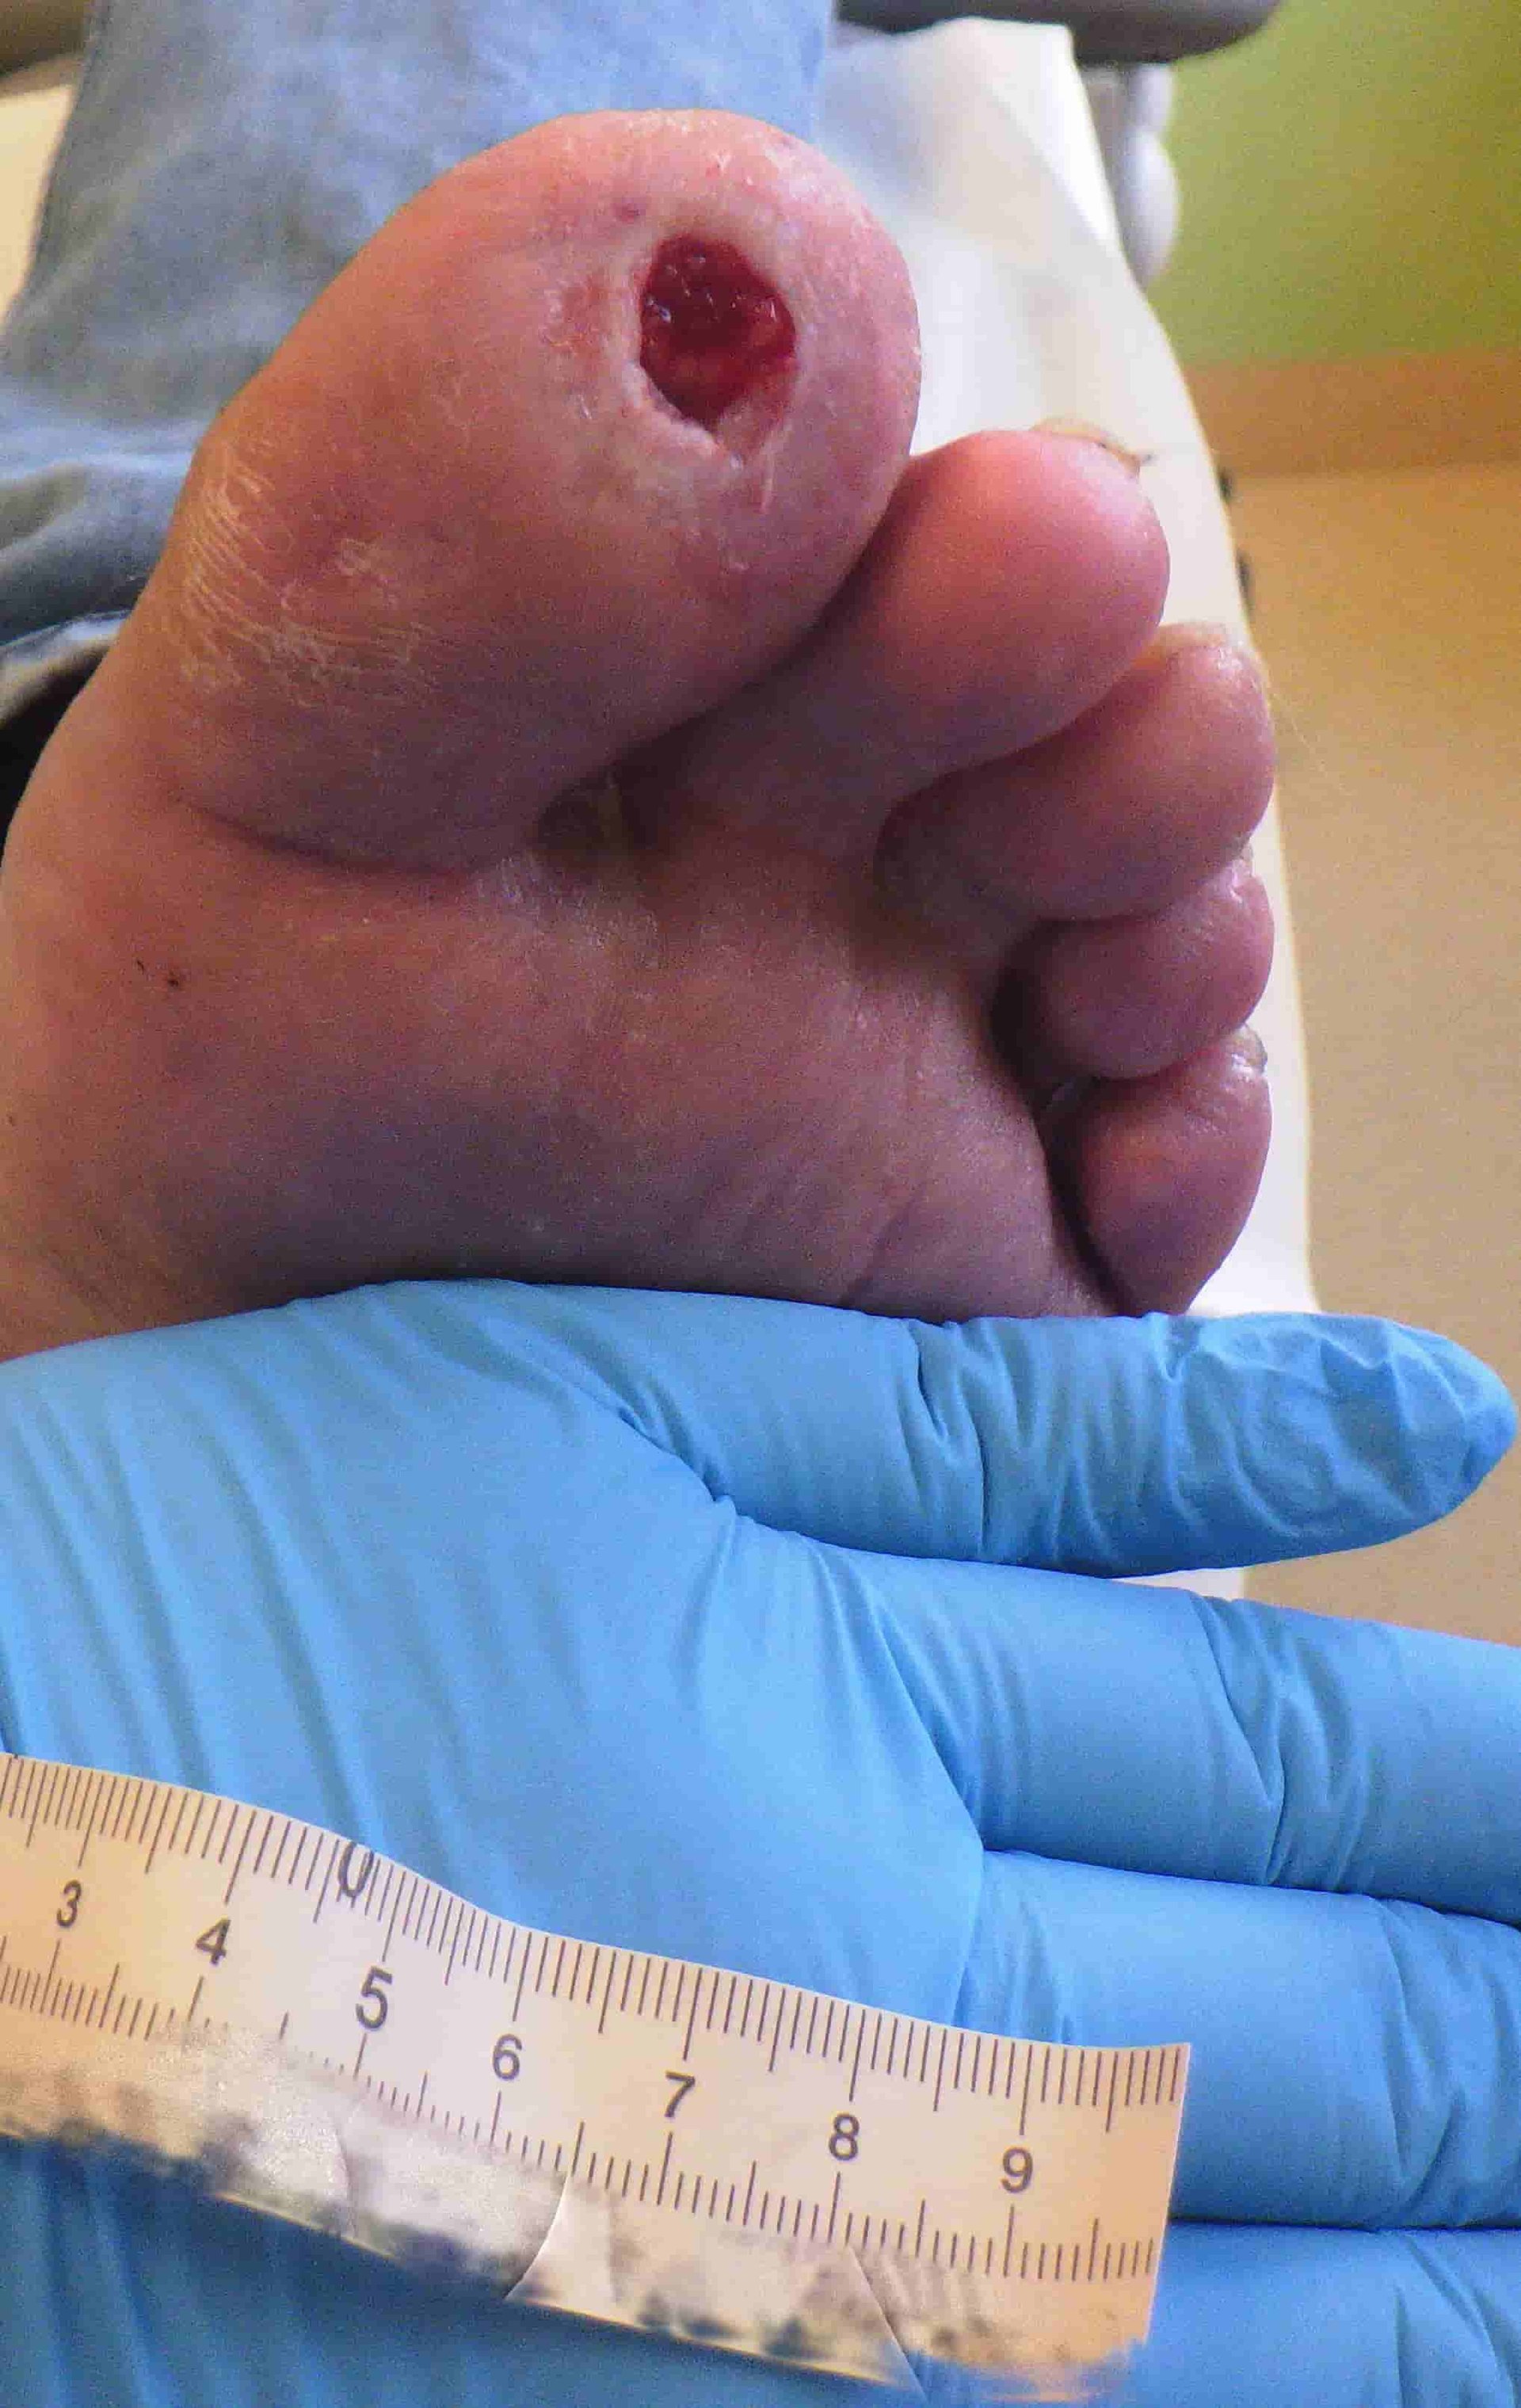

Nachdem der Patient sich den großen Zeh (D1) gestoßen hatte, erlitt er zu Beginn ein Aufpralltrauma. Die Epidermis an D1 war stark verletzt worden, ein Hämatom hatte sich gebildet. Aufgrund einer unzureichenden Wundversorgung entwickelte sich ein Abszess und mithilfe einer Blutentnahme wurden hohe Entzündungsparameter festgestellt. Nach anfänglichen mechanischen und chirurgischen Debridements entließ sich der Patient selbst frühzeitig aus dem Krankenhaus aus Angst vor einer vom Arzt angeratenen Amputation. Somit konnte eine weitere optimale Sanierung nicht stattfinden.

Nachdem sich der Patient eigenständig aus dem Krankenhaus entlassen hatte, wurde mit der strukturierten Wundversorgung und einer Kausaltherapie begonnen.

Zu Beginn der Versorgung stand die Wundreinigung und somit die Reduzierung der Keimlast im Vordergrund. Da eine pAVK im Stadium I und ein starker Nikotingenuss beim Patienten vorlagen, wurde davon ausgegangen, dass ein Sauerstoffdefizit im Bereich der Zehenkuppen besteht. Aus diesem Grund wurde bei dem Patienten nach der Wundreinigung eine Kaltplasmaanwendung durchgeführt. Durch diese Anwendung werden Bakterien abgetötet und die Sauerstoffsättigung im Bereich der Wunde steigt für eine gewisse Zeit. Dieser Effekt unterstützte die Wundheilung.

Nach der mechanischen und moderaten chirurgischen Wundreinigung mit einem Antiseptikum wurde zur Reduzierung der Keimlast eine PHMB 0,04%-haltige Creme hauchdünn auf den Wundgrund aufgetragen. Als Wundfüller und als gleichzeitigen Schutz vor einer Mazeration des Wundrandes und der Wundumgebungshaut wurde eine Hydrofaser ausgewählt. Diese saugt wie ein Docht das Exsudat aus der Wunde vertikal auf. Die Wundabdeckung erfolgte mit einer PU-Schaumkappe. Unter dieser Therapie konnte innerhalb kurzer Zeit die Wundsituation deutlich verbessert werden (s. Bild 2 und 3).